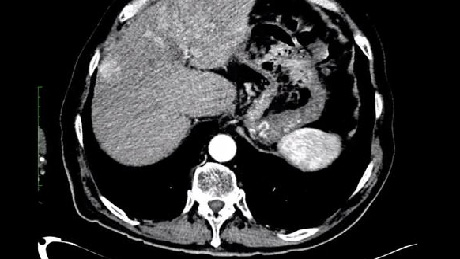

Dr. Ilan Rzadkowolsky-Raoli, of Palmetto General Hospital in Hialeah, FL, describes a 57-year-old female with a metastatic neuroendocrine lesion in her liver, straddling segments 7 and 8.